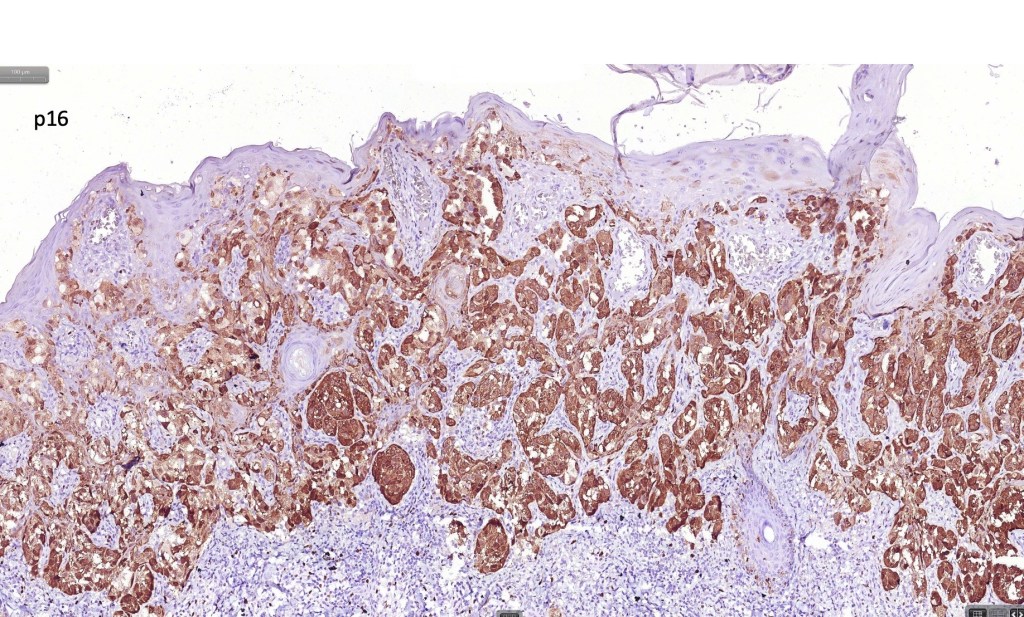

•S100, MART1 & SOX10 +ve, HMB45 +ve (superficially & lost progressively with depth), p16 +ve, p21 +ve